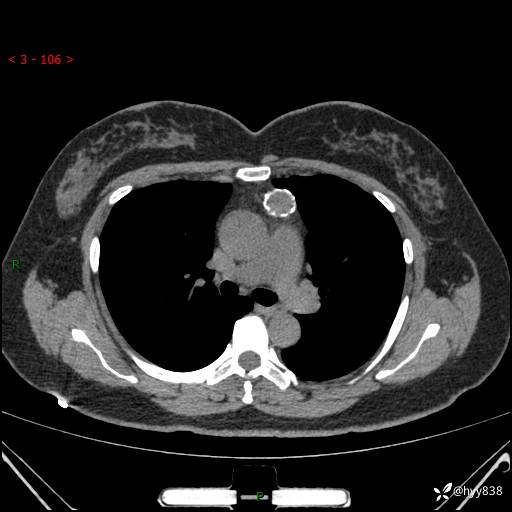

中年女性,检查发现纵隔占位3月余。圆圆的肿物,周围环绕一圈钙化---结果公布~

主诉:检查发现纵隔占位3月余。

现病史:患者于3月前体检行胸部CT检查发现纵隔占位,患者平素无明显咳嗽咳痰,无心慌、胸闷、胸痛、呼吸困难、低热、盗汗,无头痛、头晕,无腹痛、腹胀等不适。现患者欲求进一步治疗,遂来我院就诊,以“纵隔占位”收入我科。 患者自起病以来,精神可,睡眠可,饮食可,大小便正常,体重无明显改变。

胸部CT平扫+增强